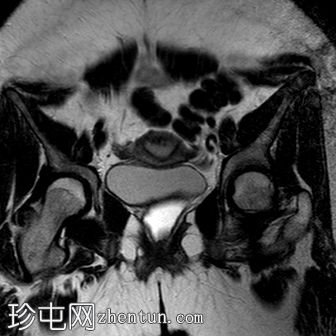

冠状位

T2加权像

阴道明显扩张,T1加权像呈中高信号,T2加权像呈高信号,耻骨联合下方可见一小局灶性隆起。

子宫大小正常,分区解剖结构正常。宫颈MRI表现正常。

右侧卵巢可见一圆形、边界清晰的囊肿,最大轴位径为4.2 x 4.3 cm,T1加权像呈低信号,T2加权像呈高信号。